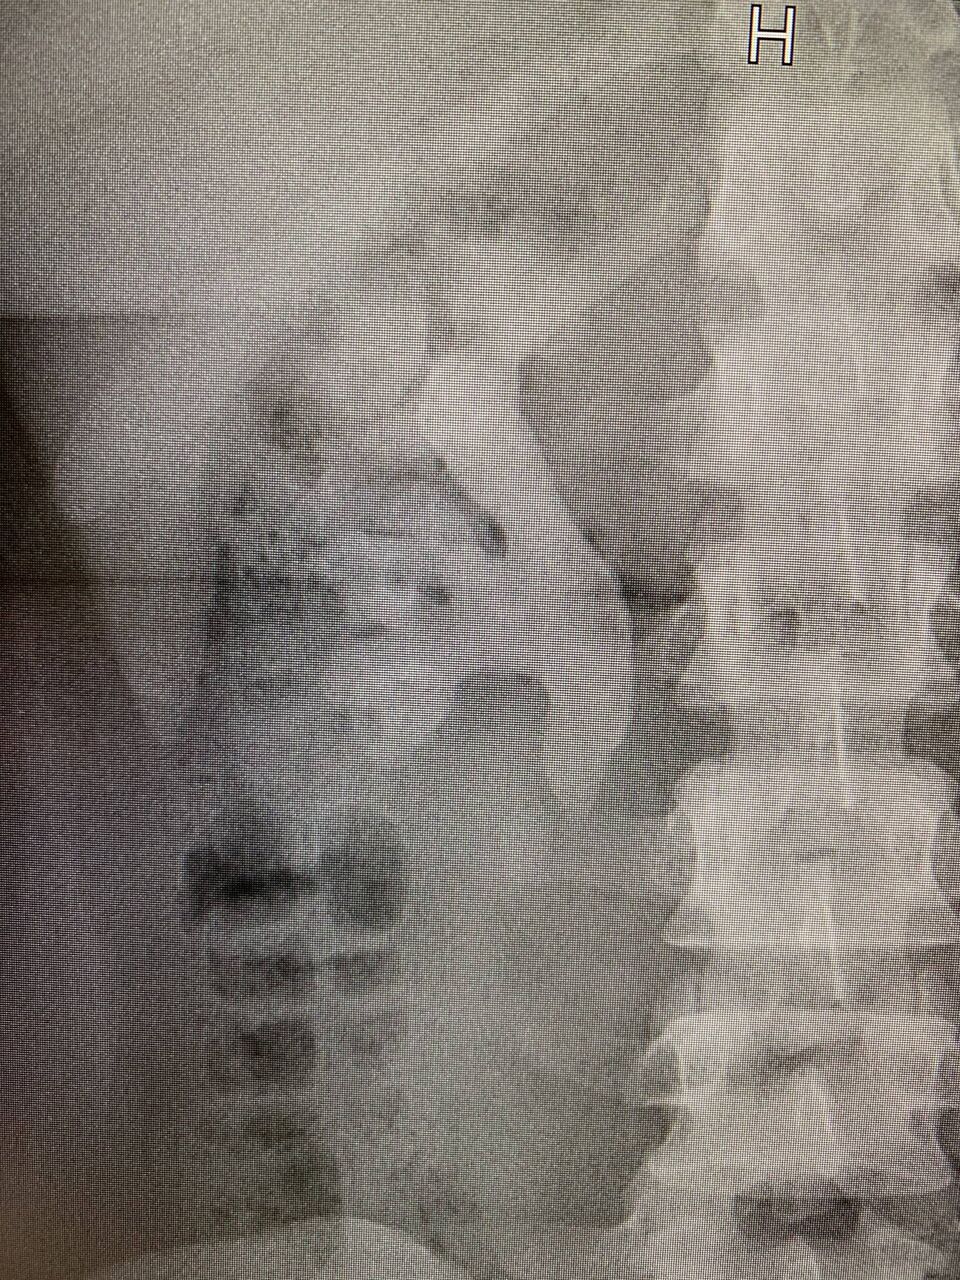

no title